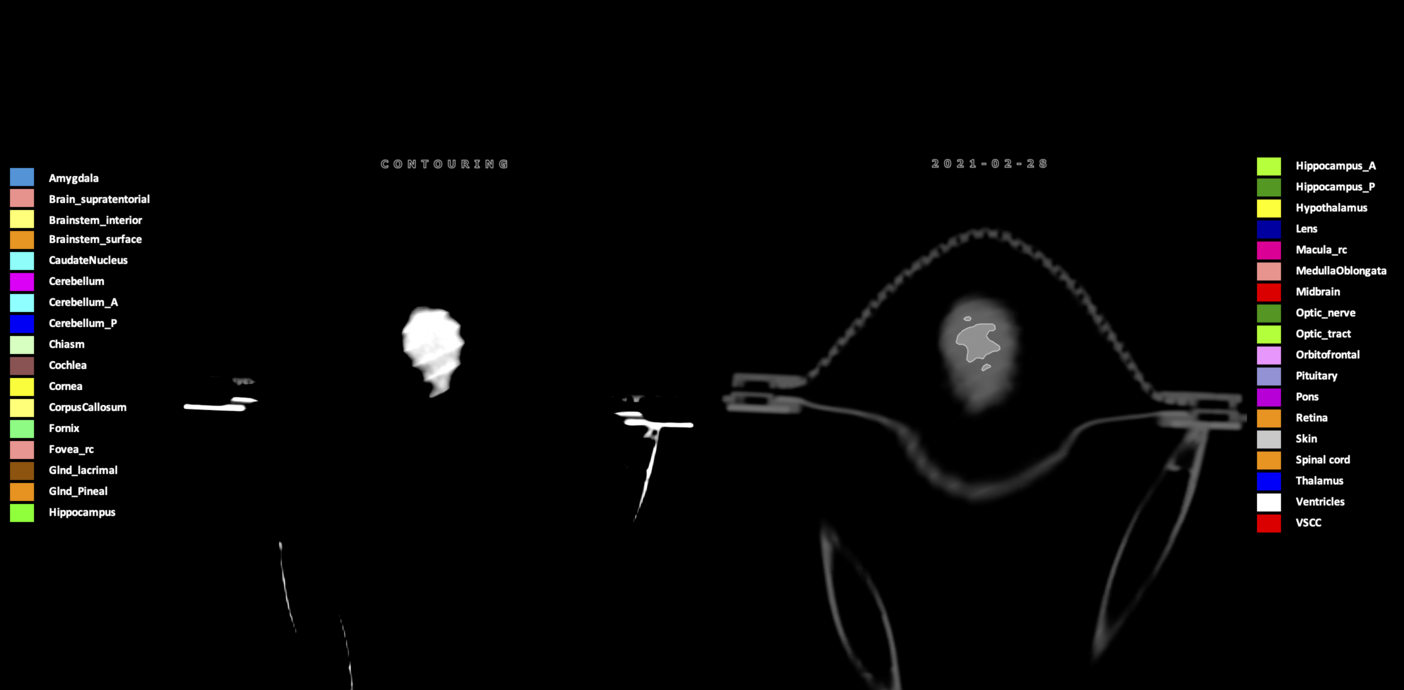

Three-dimensional delineation of the 25 consensus OARs for neuro-oncology are shown on CT (WW/WL 120/40, 3000/600), 3T MR images, (T1Gd, T2FLAIR 1mm) and 7T MR (MP2RAGE 0.7 mm). All are presented in transversal, sagittal and coronal view.